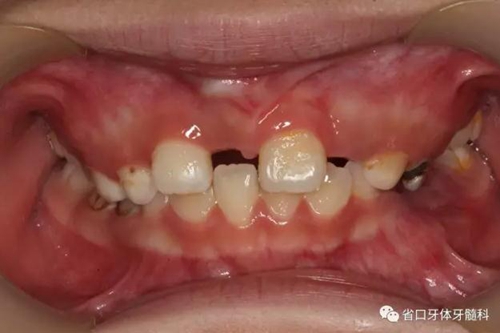

檢查:替牙列,12、21已萌出,11、22未萌,12、21間隙約5mm,右上前牙區(qū)前庭溝處見(jiàn)黏膜隆起,11牙冠未破齦。

口內(nèi)情況:正面觀